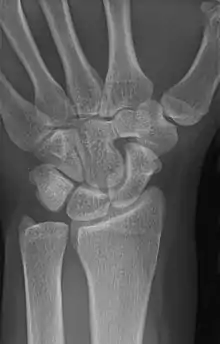

| An example of a lunotriquetral coalition, the most commonly fused carpal bones | |

Carpal coalition is the abnormal fusion of two or more carpal bones when they fail to segment during intrauterine development.[1] First described by Eduard Sandifort in 1779, carpal coalitions are often an isolated issue which connect two carpal bones in the same row of the wrist.[2] These issues are congenital and occur at various rates throughout the population.[3]

The lunate and triquetral bones are the most common carpal bones to fuse together, resulting in a lunotriquetral coalition in 1% of people. 60% of patients with a lunotriquetral coalition will have it bilaterally.[1] Among isolated incidents the capitate and hamate bones are the next most common to fuse followed by the pisiform-triquetrum, trapezium-trapezoid, scaphoid-capitate, and triquetrum-hamate.[3]